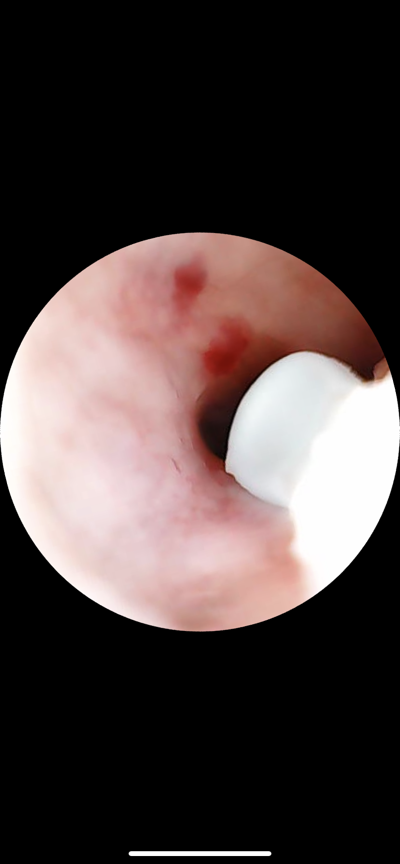

在使用 BeBird A2 的時候發現了耳道上有之前都未曾留意的小傷口,這就是使用傳統掏耳棒用力過猛可能發生的危險。可能會有朋友問,坊間有些也配置 LED 燈的掏耳棒也許一樣能發現這個傷口,但其實不然,即使一樣有燈光,如果傷口位於彎曲耳道內,被發現的機率還是很小,有可能又在清潔時重複刮傷,造成感染;但用 BeBird A2 的話不只從根源解決可能受傷的問題,就算已經有前面劣質掏耳棒造成的歷史共業,也可以謹慎躲開避免二次傷害。